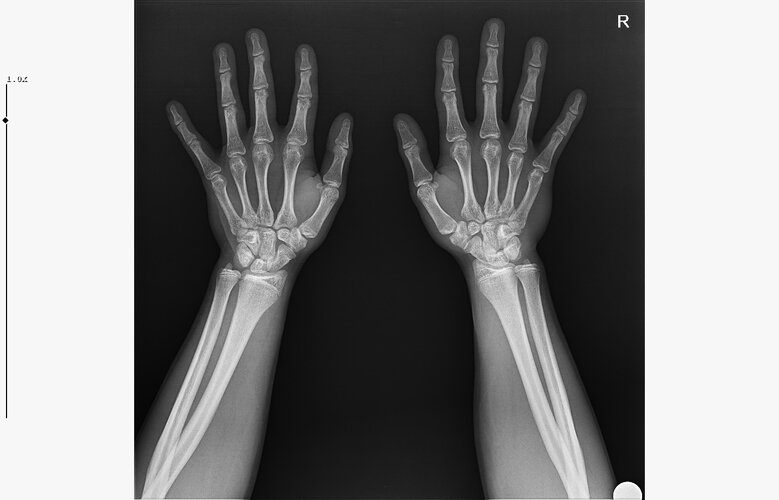

doktor bi sik bilmiyodur büyük ihtimalle plakları buraya at biz bakak

röntgeni atar mısın?

• WhatsApp Image 2026-01-07 at 00.31.08 (1).jpeg

WhatsApp Image 2026-01-07 at 00.31.08 (1).jpeg

140.5 KB · Views: 0

bilmiyo zaten,ki el plakları boy ile neredeyse hicbirsey göstermiyo bile ama tr de hangi doktora gidersen git %95inden fazlası el plağına bakcak ona göre yorum yapcak

kapanmaya baslamıs ama cok yakın degil

kemik yaşın 15 gibi 15'e çok yakın

anne baba boyun ve yaşını bilmiyorum sadece bu bilgilerle 171-175 arası diye tahmin ediyorum röntgen ile.

normalde anne babana göre 171-176 olman gerek zaten. kemik yaşın ve şuanki boyun ile yapılacak tahmin anne baban ile yapılabilecek tahminle nerdeyse birebir aynı yani büyük ihtimal o civarlar olursun bence